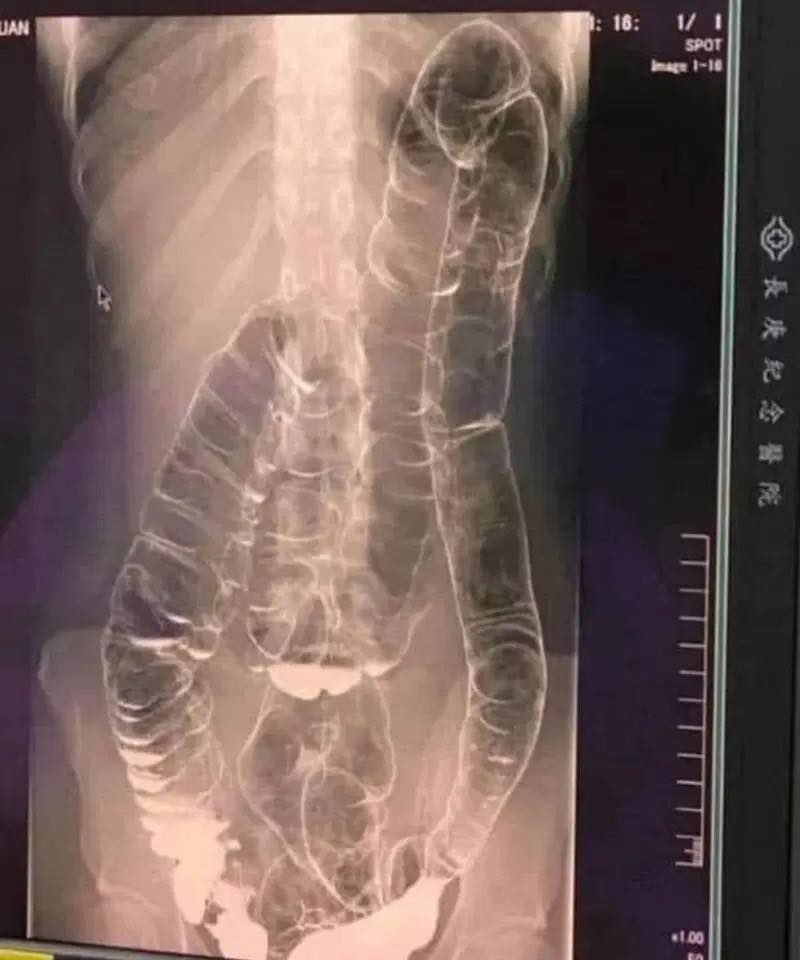

A saturated colon: when the body sounds the alarm

Who hasn’t encountered constipation? This problem, often perceived as trivial, can transform into a real nightmare if it becomes constant. This is exactly what occured to a young woman whose overloaded colon ended up dangerously dilating. So, how can we prevent this digestive disorder from taking a noticeble turn? A saturated colon When you don’t…